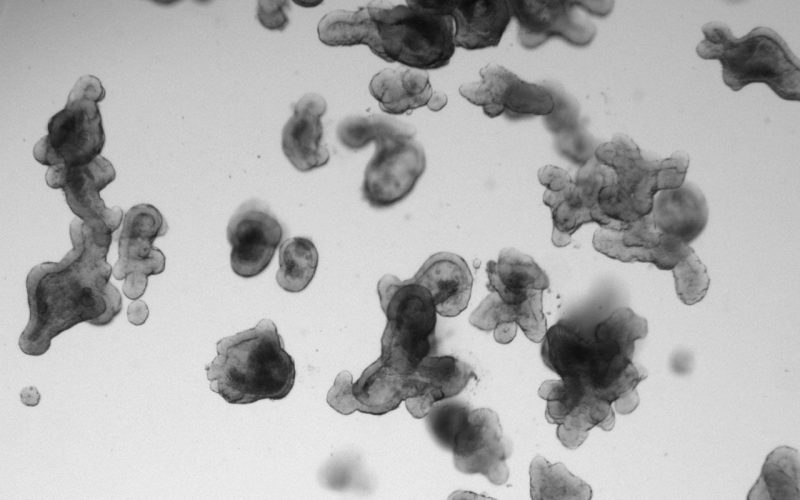

“We knew that these types of tumors mainly respond to a combination of drugs, but not exactly why,” Hugo explains. “With funding from Oncode, we were able to invest in developing a very sensitive and precise measurement system: a microscopic technique that allows us to zoom in on individual cells and also to film over time how well these cells respond to treatments.” Using the mini-tumors, the team found that inhibiting signaling pathways in cells did not happen with a single therapy, but required a combination. “This is because we need to dampen these signaling pathways much harder than thought, and than we could measure before. Thanks to our precise measurement method, we now understand that there is a self-reinforcing mechanism in the signaling pathway and that you therefore have to push more than one button to sufficiently inhibit the sometimes complex signaling pathways to fight the tumor,” said Bas Ponsioen, principal investigator on the project.